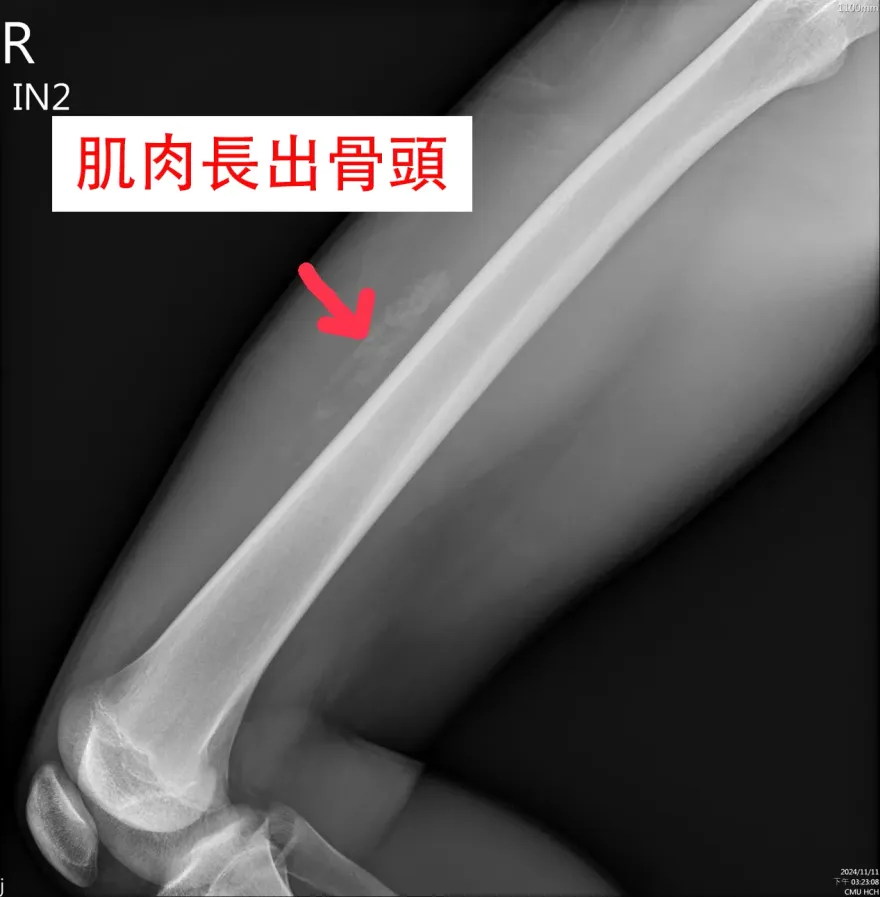

骨頭

股四頭肌

肌肉

籃球

鈣化

Walker Buehler

道奇

mlb

紅襪